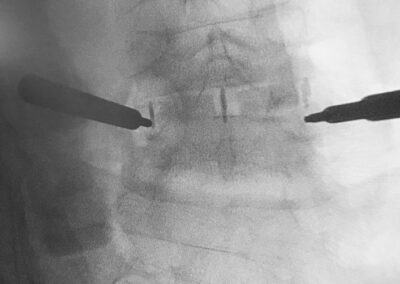

As grandes incisões são algo que as cirurgias minimamente invasivas tentam evitar ao máximo, e a colocação desses parafusos por via aberta é contraria aos benefícios que essas cirurgias visam trazer aos pacientes. Por esse motivo, a utilização da via percutânea para a colocação desses parafusos foi a solução para minimizar essa cirurgia. Esta técnica pode ser realizada em decúbito ventral quanto em decúbito lateral quando realiza-se a técnica em single position.

Através de equipamentos e próteses especialmente desenvolvidos para o acesso, a colocação dos parafusos se dá através de pequenas incisões na pele, na qual passam apenas os parafusos. O controle do posicionamento dos mesmos na vértebra é guiado pela utilização de fluoroscopia intra-operatória, que fornece a visão exata dos parafusos. Com menor dano aos tecidos e músculos adjacentes, os parafusos são fixados às vértebras e a estabilidade do nível é alcançada de maneira menos invasiva.